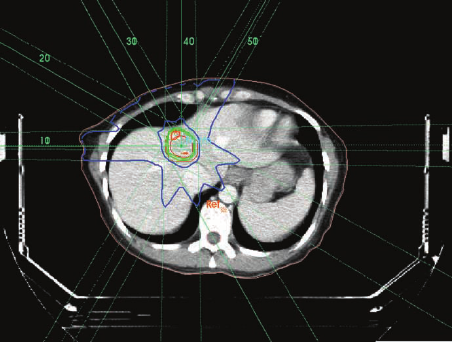

در راستای پویاسازی ارائه خدمات پزشکی و اجرایی نمودن سیاست های کلی سلامت و قانون برنامه ششم توسعه کشور، مبنی بر اجازه تجویز خدمات و انجام خرید راهبردی سازمان های بیمه گر براساس دستورالعمل ها و راهنماهای بالینی توسط وزارت بهداشت «ابلاغ شناسنامه و استاندارد خدمت رادیوتراپی به روش SBRT/SRS» به تصویب رسیده و از تاریخ ابلاغ قابل اجرا است.